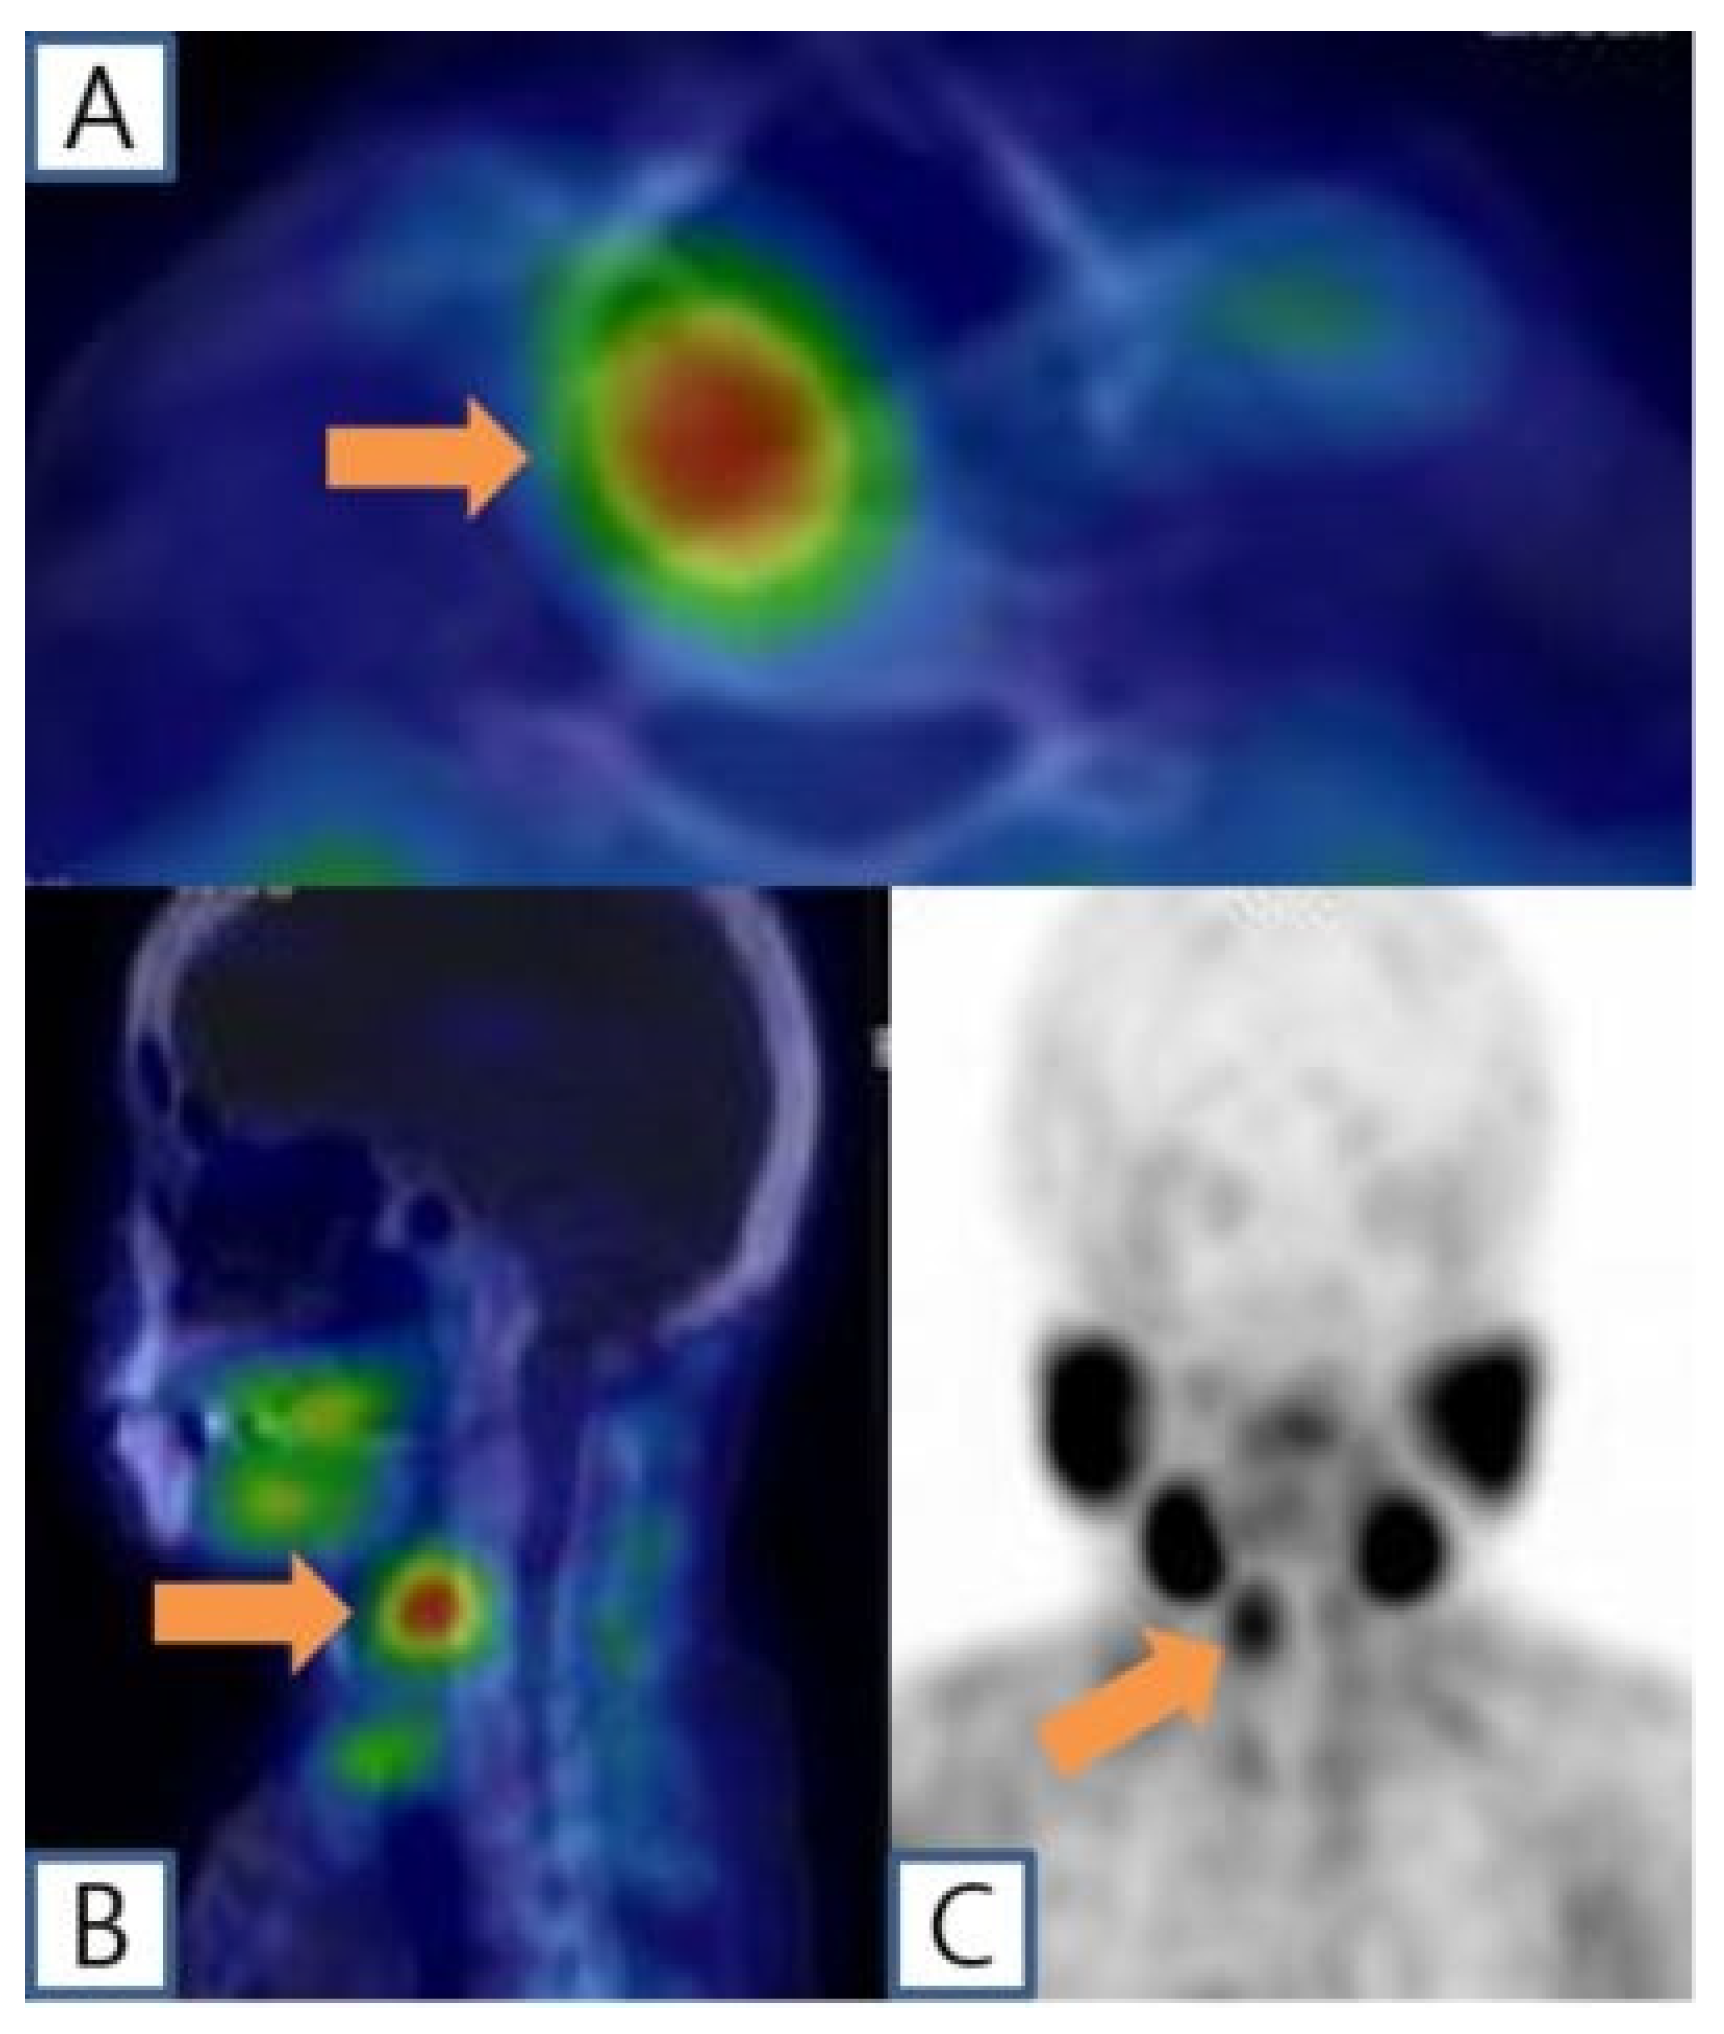

A 51-year-old female patient with end-stage renal disease on dialysis was referred by the nephrology department due to suspected osteoporosis and the presence of osteoblastic lesions. Laboratory results indicated elevated serum calcium (10.4 mg/dL; normal range: 8.4~10.2 mg/dL), intact parathyroid hormone level (383 pg/mL; normal range: 12.0~65.0 pg/mL), and low serum phosphate (1.71 mg/dL; normal range: 2.3~4.7 mg/dL), as well as 25-OH vitamin D (13.6 ng/mL; normal range: 20.1~100 ng/mL). Subsequent cervical computed tomography (CT) scans displayed a well-defined enhancing mass measuring about 2.6cm in the retropharyngeal space at the upper level of the right thyroid cartilage. Based on clinical symptoms and radiological findings, additional parathyroid imaging was performed to precisely locate the suspected parathyroid adenoma. The parathyroid scan showed the presence of an upper right parathyroid adenoma in the retropharyngeal region, prompting the patient to seek surgical consultation (Figure 1). A transverse incision of approximately 5 cm was made slightly to the right of the midline of the neck, exposing the sternocleidomastoid (SCM) muscle. Following the lateral retraction of the SCM muscle, the right thyroid gland was discerned, and an incision was performed to reach the retropharyngeal space at the hyoid bone level. Enlarged lymph nodes were observed in the adjacent region, and by gently displacing the thyroid to the left, the parathyroid mass situated in the retropharyngeal space was revealed. Careful dissection was carried out to separate the retropharyngeal mass from the surrounding tissues. A portion of the excised mass was subjected to frozen section analysis, confirming its parathyroid origin. Intraoperative intact parathyroid hormone (iPTH) levels were measured and revealed a gradual reduction after the removal of the mass. The iPTH levels decreased to within the normal range as seen via serum testing 20 min after tumor removal. Lobectomy was performed through conventional techniques without injury to the recurrent laryngeal nerve and inferior parathyroid gland. No postoperative complications were observed, and the patient was discharged on the 5th day post-surgery. Subsequent pathology results of the thyroid nodule confirmed papillary thyroid cancer with no extrathyroidal extension or neural involvement and the retropharyngeal mass was diagnosed as a parathyroid adenoma (Figure 2). After the surgery, the patient’s blood tests showed that serum calcium (8.61 mg/dL), parathyroid hormone (32 pg/mL), and serum phosphate (4.57 mg/dL) levels had all returned to within the normal range. Ultimately, significant clinical improvement was achieved, and the patient is now under regular observation and follow-up (Figure 3).

Figure 2. [99m Tc]Tc-MIBI single-photon emission computed tomography combining computed tomography (SPECT/CT) scintigraphy showing the right retropharyngeal lesion with sustained radiotracer uptake on the delayed images (A,B) (orange arrow). Maximum-intensity projection image (C) (orange arrow).